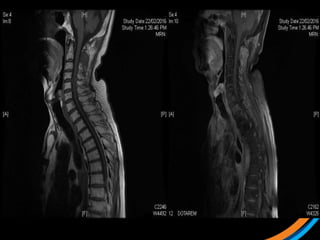

Case study 1 (Patient 001)

• 70 Male, ECOG 0

• Metastatic Cholangioca since 2006

• Progressive C2 lesion causing neck pain

 1) Review the images

 2) Target the lesion

• #31 Sag T1, Sag T1c

• #32 Ax T2 Ax T1C

• #33 Sag STIR